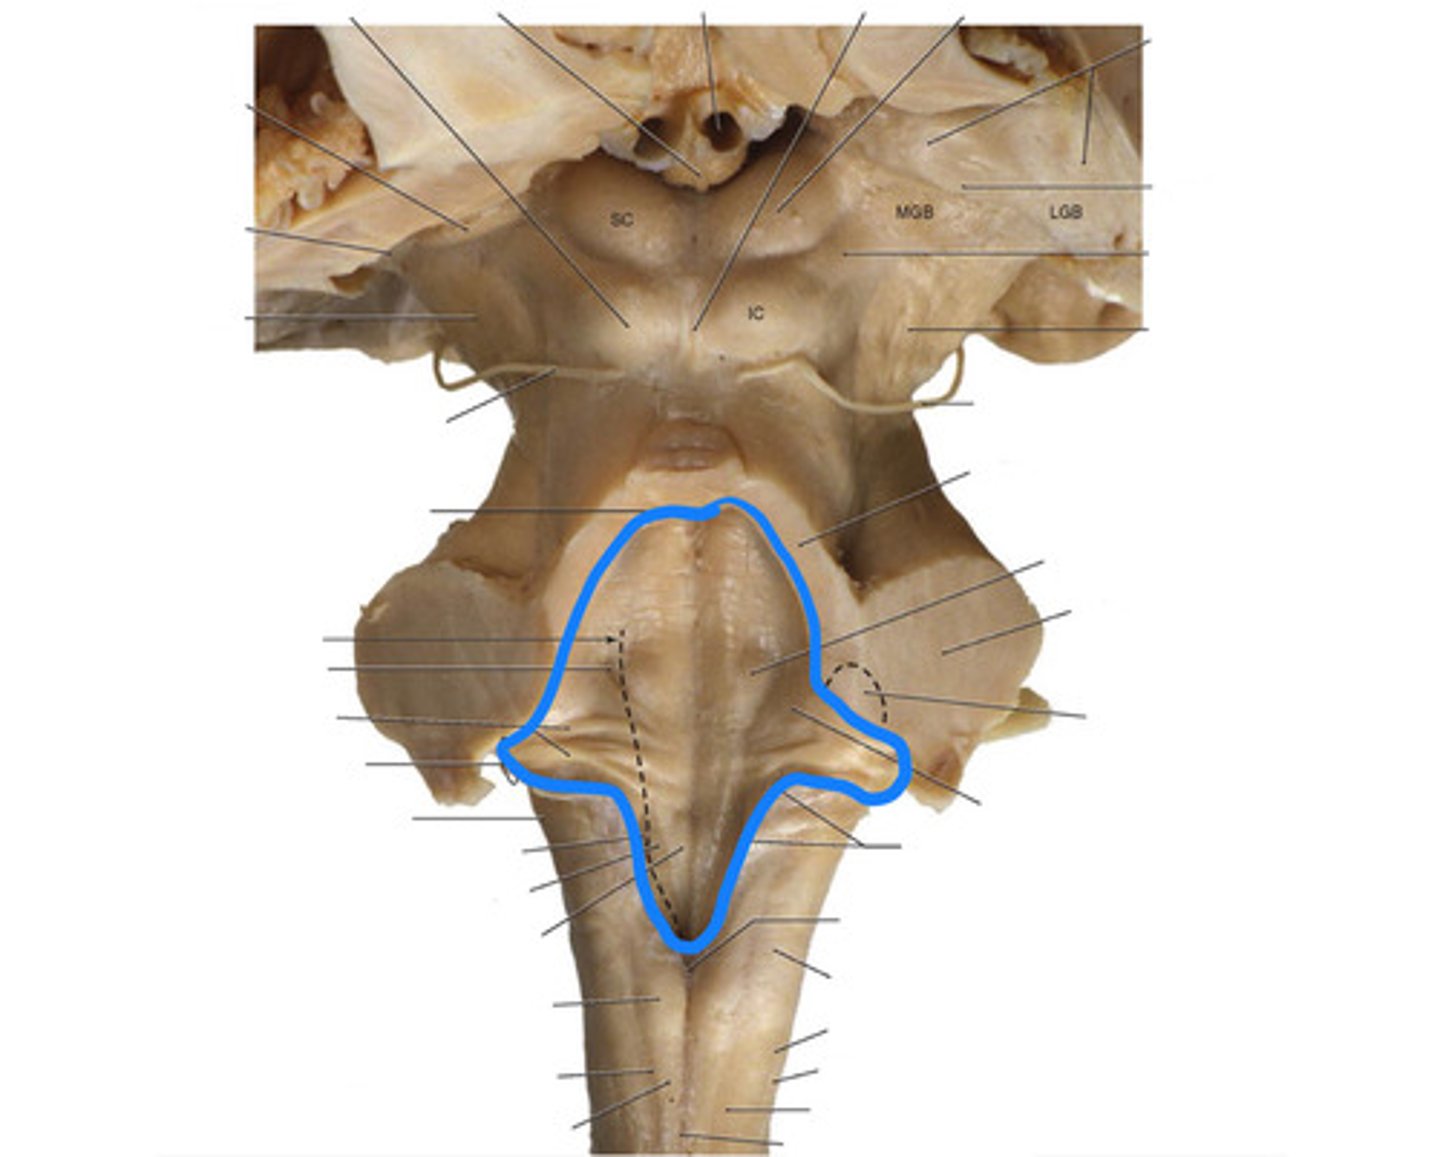

What anatomical aspect of the 4th ventricle is considered its floor?

ventral

refers to the floor of the 4th ventricle

rhomboid fossa

What forms the floor (rhomboid fossa) of the 4th ventricle?

dorsal surfaces of pons tegmentum and open medulla

inferior angle of the floor of the 4th ventricle

obex

vertical groove running in the floor of the 4th ventricle that separates it into right and left halves

dorsal median sulcus

vertical groove lateral to the dorsal median sulcus of the 4th ventricle

**same one that separated the alar and dorsal plates in the neural tube during development

sulcus limitans

refers to most of the floor of the 4th ventricle lateral to the sulcus limitans

**namesake nuclei are here

vestibular area

triangular region located in the caudal portion of the rhomboid fossa of the 4th ventricle, where the dorsal motor nucleus of CN X is

vagal trigone

Which parasympathetic nucleus is found in the vagal trigone of the 4th ventricle?

dorsal motor nucleus of X

triangular region located most medially in the caudal portion of the rhomboid fossa of the 4th ventricle, where the CN XII nucleus is

hypoglossal trigone

part of the 4th ventricle superior to the vagal and hypoglossal trigones (still medial to the sulcus limitans)

medial eminence

small bump located in the caudal portion of the medial eminence which forms from the motor fibers of CN VII as they wind around the underlying CN VI nucleus

facial colliculus

pigmented area that looks blue near the superior aspect of the sulcus limitans; cluster of noradrenergic cells

locus ceruleus

fibers that run horizontally in the central region of the rhomboid fossa of the 4th ventricle

stria medullares

area that helps to make the walls of the obex and is thought to be the "vomit trigger"

area postrema

floor of 4th ventricle

rhomboid fossa

sulcus limitans

floor of 4th ventricle lateral to sulcus limitans

vestibular area

vasal trigone

hypoglossal trigone

medial eminence

small bump in caudal portion of medial eminence

facial colliculus

stria medullares